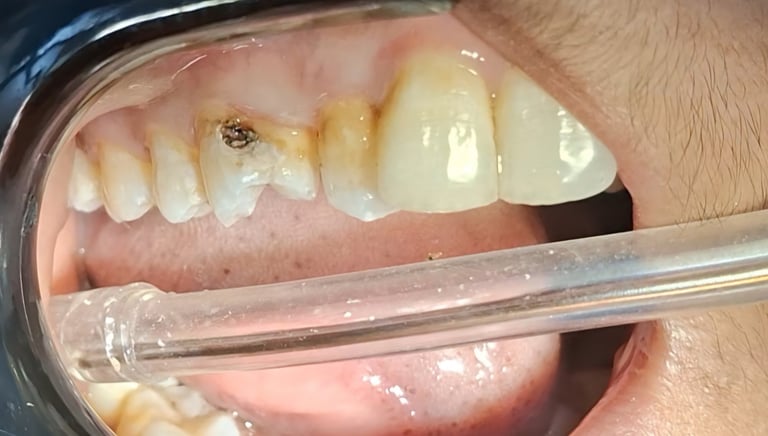

Tooth Colored Filling in Shyamal, Ahmedabad

Tooth-colored fillings are used to restore decayed or broken teeth while maintaining a natural appearance. These fillings blend seamlessly with your tooth color and help preserve your smile.

Before

After

All images shown here are real tooth colored filling cases treated at our clinic with patient consent.

At Shree Dental Care, cosmetic fillings are placed carefully with a focus on comfort, precision and long-term durability. We ensure minimal tooth cutting and natural-looking results.

If you are looking for aesthetic tooth colored filling in Shyamal, Ahmedabad, you can book an appointment with our clinic.